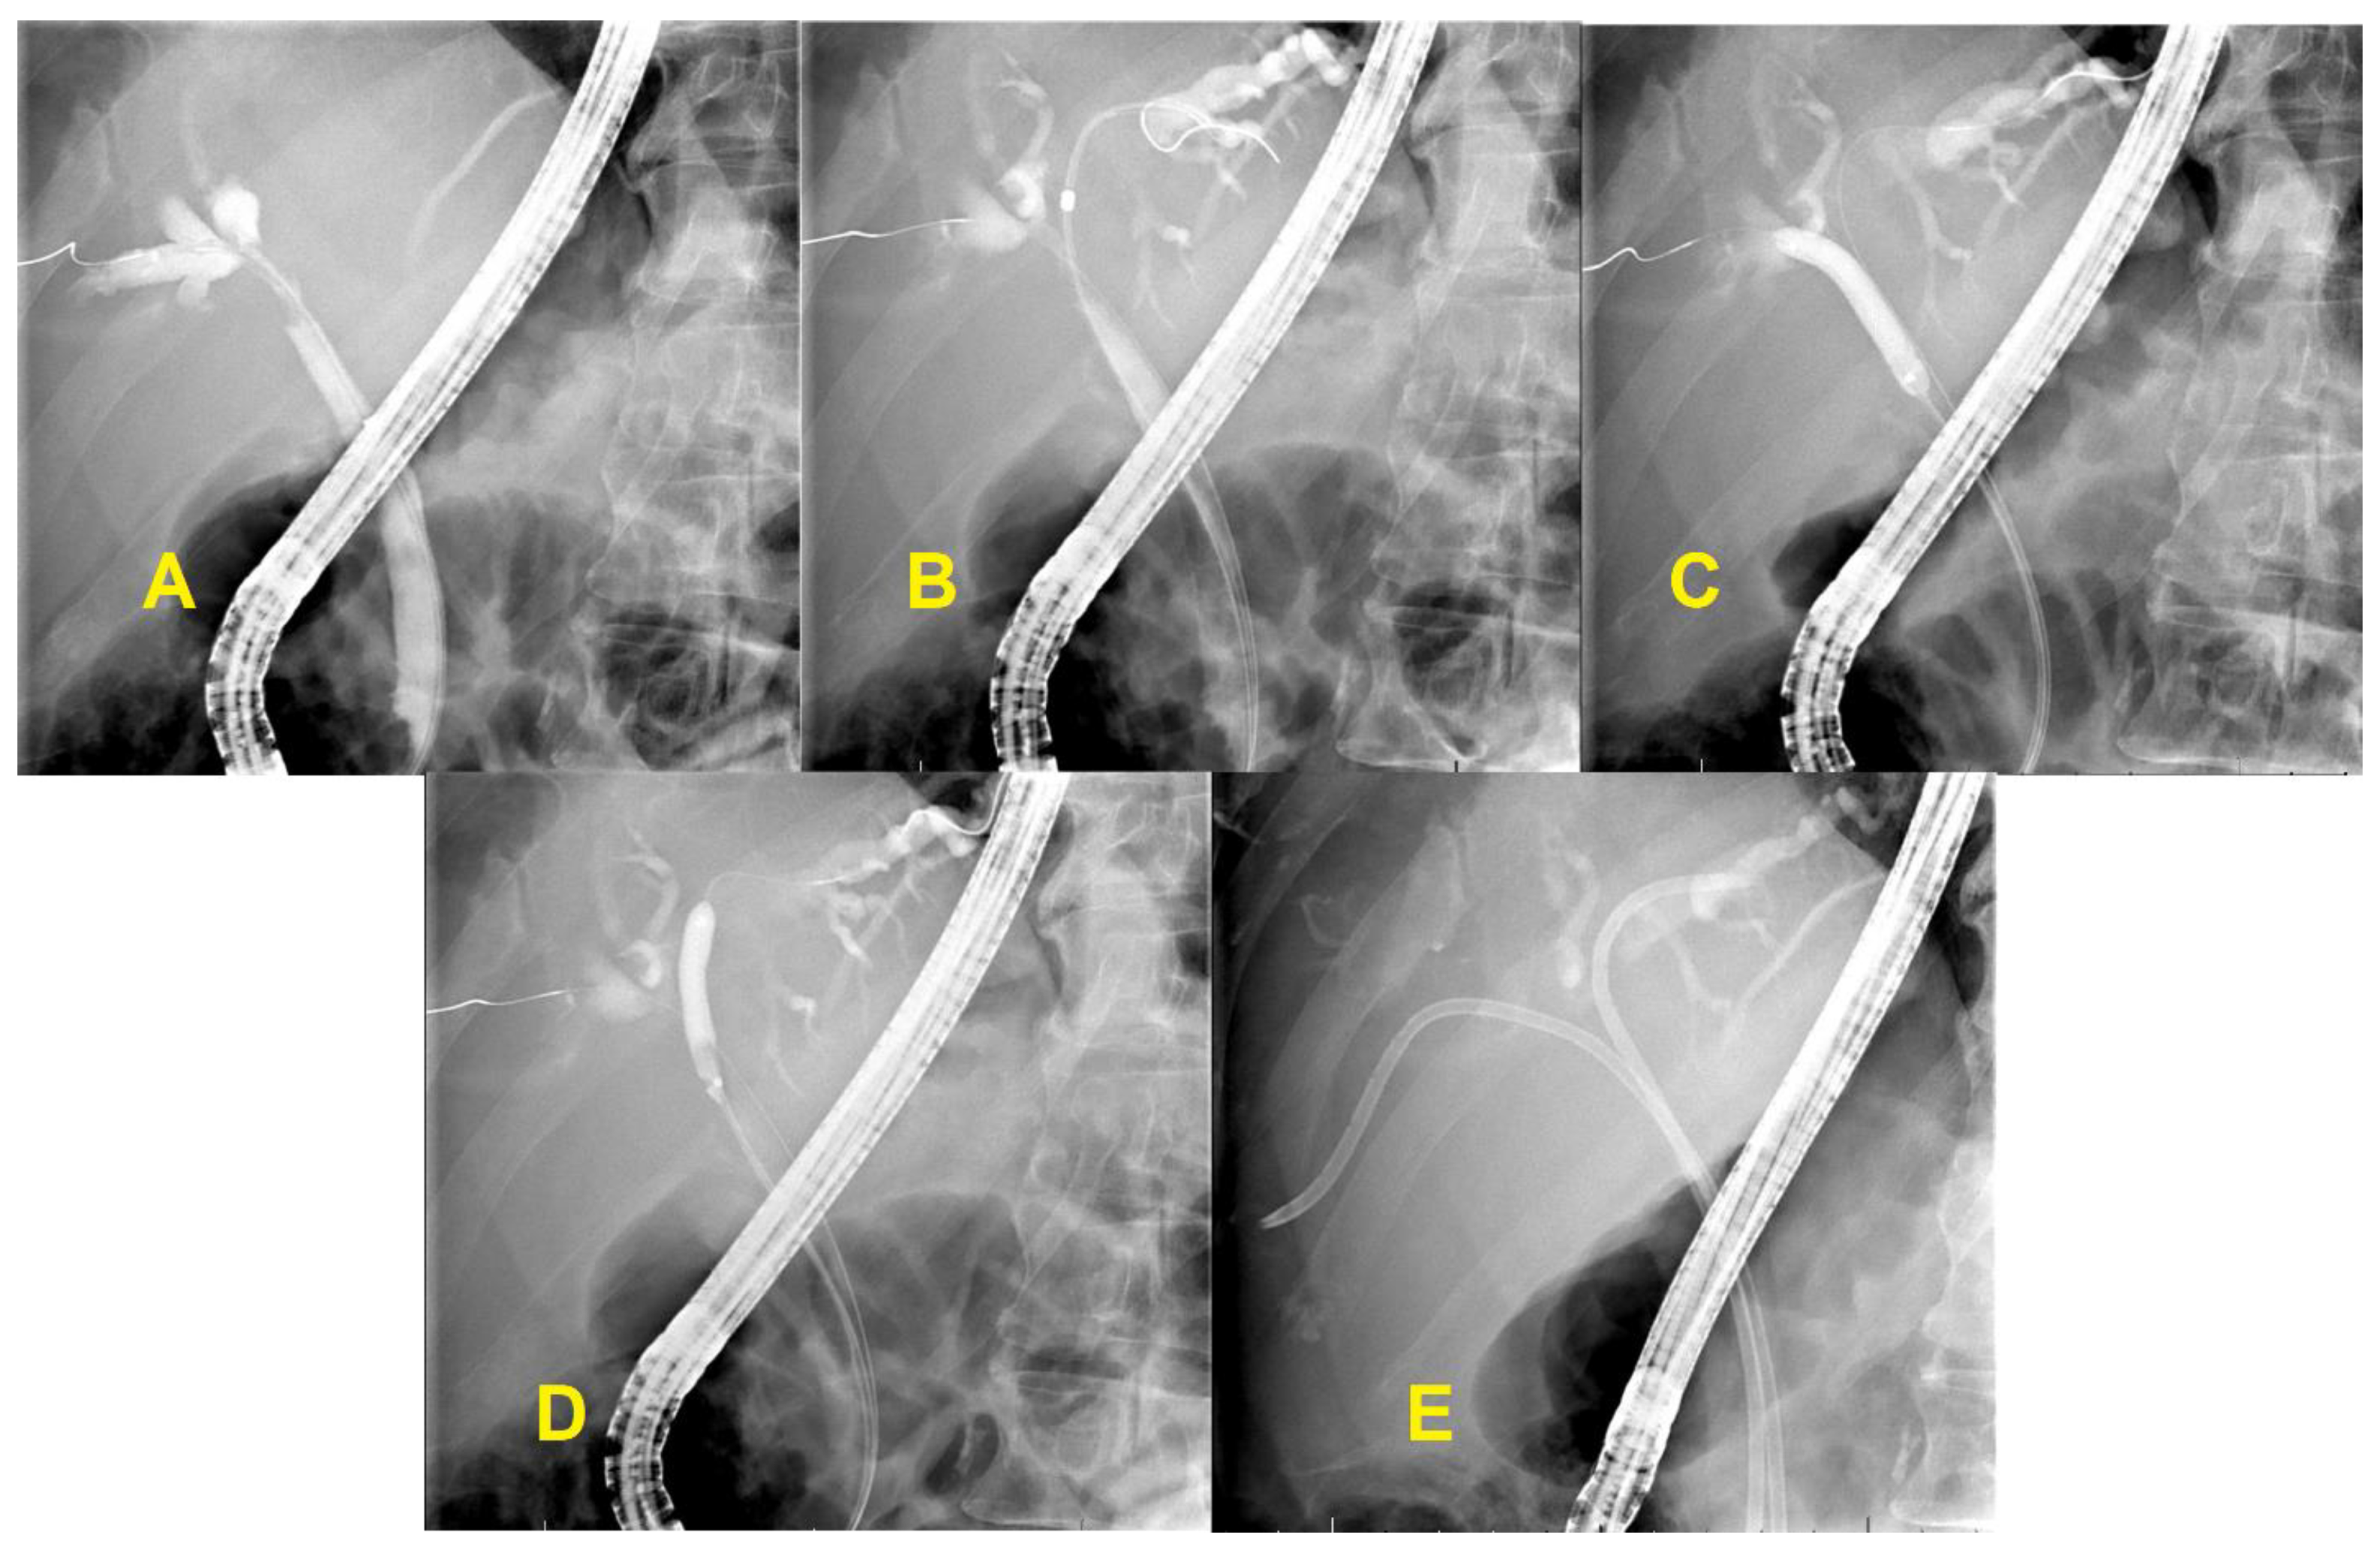

3.3. Unresectable Hilar Malignant Biliary Stricture (HMBS)